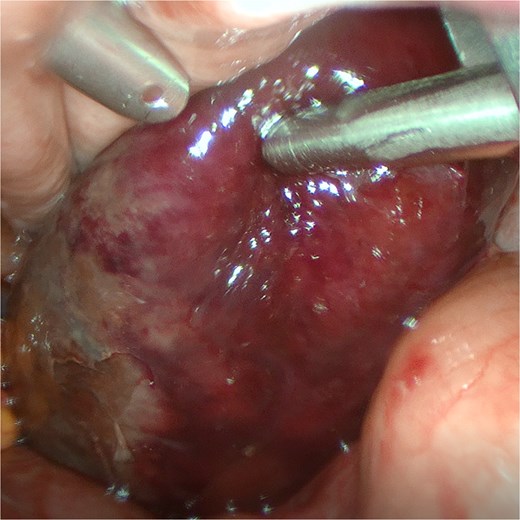

An 82-year-old female presented to the emergency department with a 2-day history of right upper quadrant pain accompanied by nausea and vomiting. The patient was hunched and thin, with a body mass index of 15.0 kg/m2 (Fig. 1). Physical examination revealed abdominal tenderness and a positive Murphy’s sign. Routine blood examination showed a white blood cell count of 16.5 × 10 [5], C-reactive protein of 3.83 mg/L, and normal liver function and electrolytes. A non-contrast abdominal computed tomography (CT) scan (Fig. 2) and gallbladder US (Fig. 3) were performed. We administered analgesics and antibiotics for 24 hours based on US and CT findings indicating impacted stones in the neck of the gallbladder. However, the patient’s symptoms of persistent abdominal pain did not improve, prompting us to proceed with laparoscopic exploration. During the operation, a necrotic gallbladder was identified within the confined space of the abdominal cavity (Fig. 3). Subsequently, intraoperative puncture decompression of the gallbladder was performed, followed by exploration via manipulation and rotation of the gallbladder using laparoscopic instruments (Fig. 4). The gallbladder was found to be completely mobile and had undergone a 360°clockwise torsion (Fig. 5). We successfully performed a laparoscopic cholecystectomy and pathological examination showed acute gangrenous cholecystitis. The patient was discharged on the fourth postoperative day.